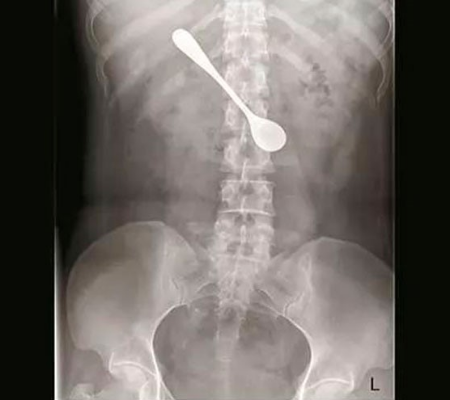

Mulher engole colher de 13cm ao tentar retirar espinha de peixe

Peixes são deliciosos, mas todo mundo sabe que precisa de muito cuidado ao comê-los. Foi o caso de uma paciente conhecida como Lili, ela ficou com uma espinha de peixe presa em sua garganta e tentou usar uma colher para remover. O resultado disso tudo? A mulher acabou engolindo a colher também.

O mais inusitado em toda a história é que a mulher não foi ao hospital imediatamente após engolir a colher. Segundo ela, seria muito trabalho visitar um médico. Depois de um tempo, ela foi para um hospital no sudeste da China, onde o médico solicitou um raio-x para localizar o objeto.

O utensílio estava preso ao duodeno de Lili, causando inchaço e danos ao órgão, e ela precisou passar por uma endoscopia de emergência para conseguir removê-lo.

“Como a colher estava em uma posição mais horizontal, nós a ajustamos cuidadosamente antes de puxá-la de forma vertical,” explicou o Dr. Sun Tingji, que atendeu a paciente. Apesar do susto, o procedimento foi bem-sucedido e Lily recebeu tratamento posterior, ela já teve alta e os médicos esperam uma recuperação total em breve.